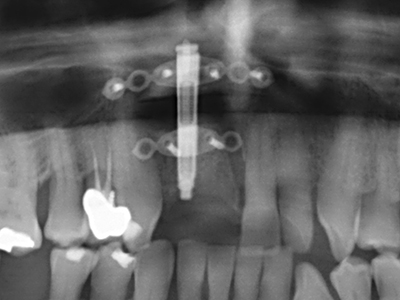

Quando le procedure chirurgiche vengono eseguite sull'osso nelle immediate vicinanze di strutture sensibili, come vasi sanguigni o nervi, gli strumenti rotanti pongono un rischio significativo di lesione iatrogena. I dispositivi piezoelettrici possono essere utili per la preparazione delle coperture ossee e la rimozione del tessuto duro in prossimità dei nervi, in particolare per la loro esposizione dopo una lesione iatrogena, ma anche durante la lateralizzazione dei nervi per le procedure di resezione e ricostruzione o il posizionamento di impianti (figg. 17-20). Il contatto leggero tra puntina piezoelettrica e nervo non causa generalmente danni, ma se si procede senza prestare attenzione con movimenti a sega o raccordi con residui di substrati ossei possono verificarsi danni al nervo temporanei o anche permanenti. Il rischio di danno, tuttavia, è considerato sostanzialmente inferiore al rischio presente utilizzando seghe o frese (Pereira, Gealh et al. 2014).